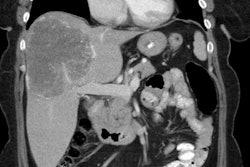

|

Benign adrenal lesion with FDG uptake: The patient shown below had a left adrenal mass which had remained stable for 2 years (white arrow). The stability over time and CT features would be consistent with a benign adrenal lesion- likely an adenoma. Note the marked FDG uptake within the mass on PET imaging (black arrows). Benign adrenal adenomas can accumulate FDG resulting in false positive exams. The use of PET/CT has been shown to improve the specificity of the PET exam. |